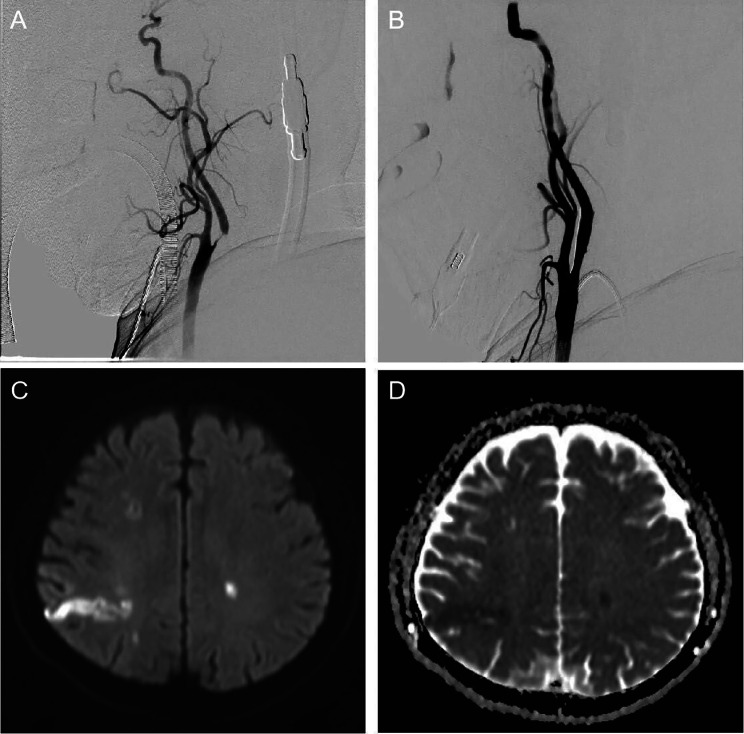

The patient underwent carotid artery stent implantation under intravenous compound inhalational anesthesia with significant improvement in carotid artery stenosis after interventional surgery (Fig. 2A and B). After waking up from anesthesia, the patient became severely aphasic, producing only a few meaningless and poorly articulated syllables (NIHSS score 4) with severe cognitive impairment (MMSE score 18). The patient immediately underwent cranial CT and carotid ultrasonography, and no cerebral hemorrhage or carotid artery occlusion was found. Immediately afterward, head magnetic resonance imaging (MRI) was performed, and acute cerebral infarction lesions were found in the right parietal lobe (Fig. 2C and D).

Fig. 2.

Comparison of preoperative and postoperative DSA images and postoperative MRI images. (A) DSA image showing severe stenosis of the right internal carotid artery. (B) Carotid artery stenosis improved significantly after carotid stenting. (C) DWI image showing high-intensity signals in the right parietal temporal lobe. (D) ADC showing low-intensity signals in the right parietal temporal lobe. DSA: Digital subtraction angiography; MRI: Magnetic resonance imaging; DWI: Diffusion Weighted Imaging; ADC: Apparent diffusion coefficient